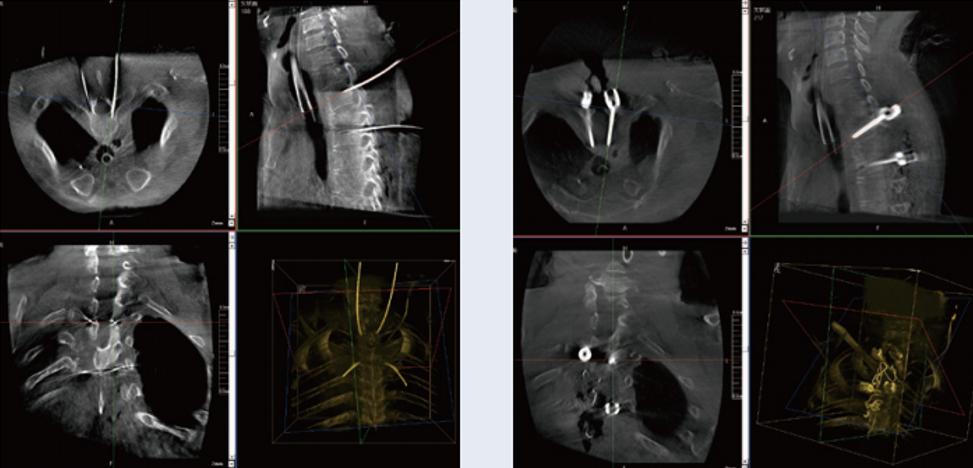

螺釘規(guī)劃后的圖像

植入螺釘后的圖像

術(shù)中三維C臂與骨科導(dǎo)航機(jī)器人配合應(yīng)用,實(shí)現(xiàn)準(zhǔn)確定位,確保了手術(shù)安全、高效完成。術(shù)后二維、三維影像顯示手術(shù)效果良好,達(dá)到預(yù)期目的。

普愛醫(yī)療三維C臂提供了高質(zhì)量的術(shù)中實(shí)時(shí)三維圖像數(shù)據(jù),保障了骨科導(dǎo)航機(jī)器人手術(shù)的準(zhǔn)確度和安全性,取得不錯(cuò)的手術(shù)效果。同時(shí),三維C臂特有的斷層成像,能幫助醫(yī)生在術(shù)中非常直觀地判斷螺釘植入的準(zhǔn)確度。